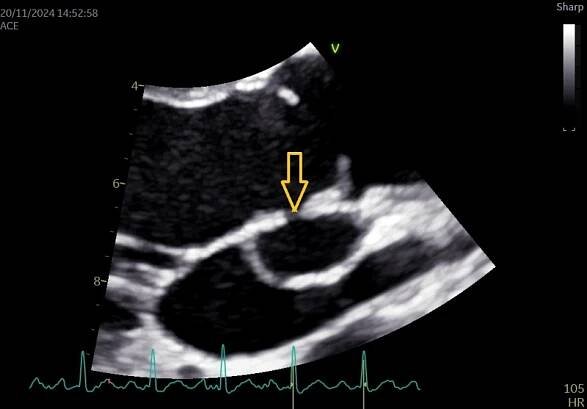

Endokarditida - vegetace na aortální chlopni na TEE

Infekční endokarditida je zánět vnitřního povrchu srdce neboli endokardu, který je způsobený mikroorganismy a postihuje zejména srdeční chlopně.